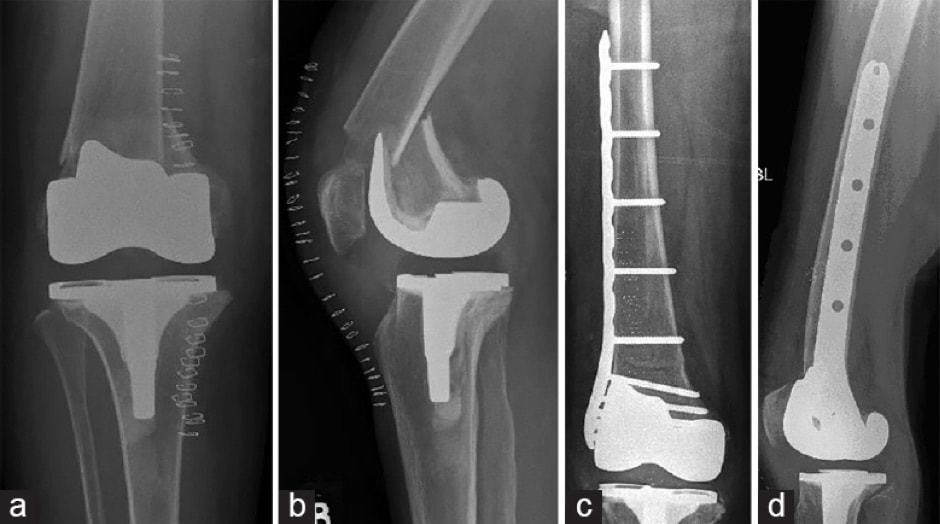

Knee Replacement, for a failed Knee fracture surgery (plates and screws Screws In Knee Surgery Orthopaedic surgeons can use screws, pins, plates or wires to reconnect your bone pieces. You've had surgery to remove orthopedic hardware such as metal screws, pins, or plates. Loose screws don’t happen often. Three types of bone screws are used. But occasionally a screw can back out, unscrew, and irritate tendons or nerves. Cortex screw thread is designed for diaphyseal. Screws In Knee Surgery.

From www.researchgate.net

(PDF) NavigationAssisted Total Knee Arthroplasty for the Knee Screws In Knee Surgery When they do, it may mean that something went wrong with the way your bones healed. Three types of bone screws are used. Cancellous bone screws designed for cancellous bone. The surgery involves removing either a wedge of bone from the outside of your knee or opening up a wedge of bone on the inside of. Orthopedic fixation is fundamentally. Screws In Knee Surgery.